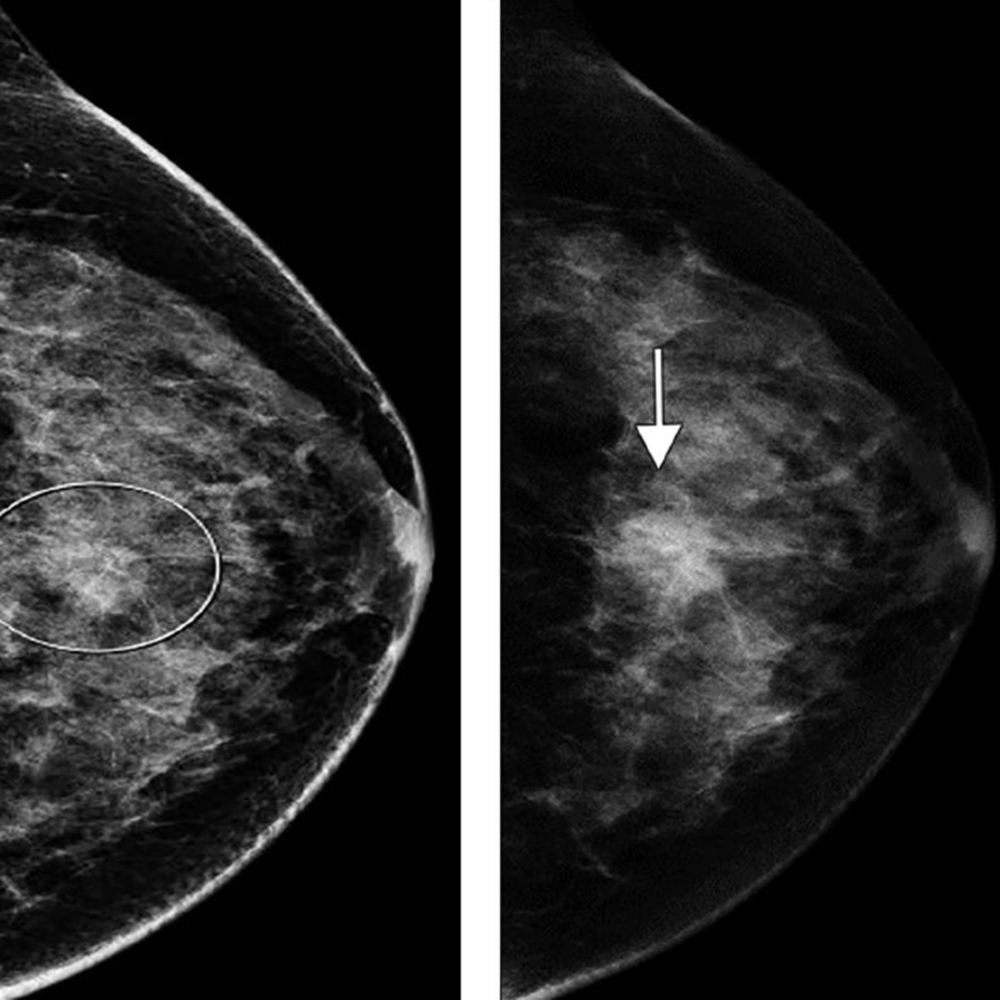

As of this writing, CEM has been approved by the FDA only as a diagnostic examination. For this reason, imaging practices are primarily using CEM as an alternative to MRI, when MRI cannot be performed. CEM is also used as a problem-solving tool in cases of known or suspected lesions. It is used in cases of recalls from screening; breast cancer staging (Fig. 1); evaluation of symptomatic breasts; troubleshooting complicated mammographic and ultrasound imaging, although this is rare; and treatment response to neoadjuvant chemotherapy. Some institutions are using CEM for supplemental breast cancer screening of patients who cannot undergo MRI, have dense breast tissue, or need additional screening.